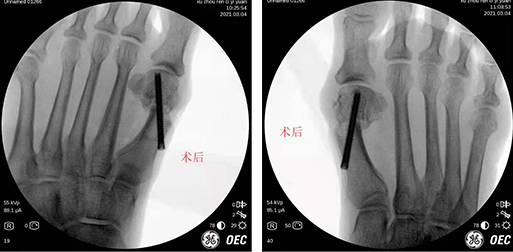

3月7日,必威官方首页官网betway石荣剑副院长团队为74岁女患者进行了双足踇外翻微创矫形内固定手术。

在必威官方首页官网betway足踝科,门诊医生给老人进行了检查,老人是双足踇外翻畸形伴拇囊炎,随后,石荣剑副院长徐明亮主任魏笛医生团队采用第三代微创踇外翻矫形技术,为老人进行了双足踇外翻截骨矫形内固定+拇收肌松解术。术中使用低频超声骨刀微创截骨,向外侧轻推跖骨头端,切口微小,几乎未出血,截骨后位置满意,以空心螺钉固定,手术顺利结束。患者术后第二天就下地活动,对手术效果很满意,明天即将出院。